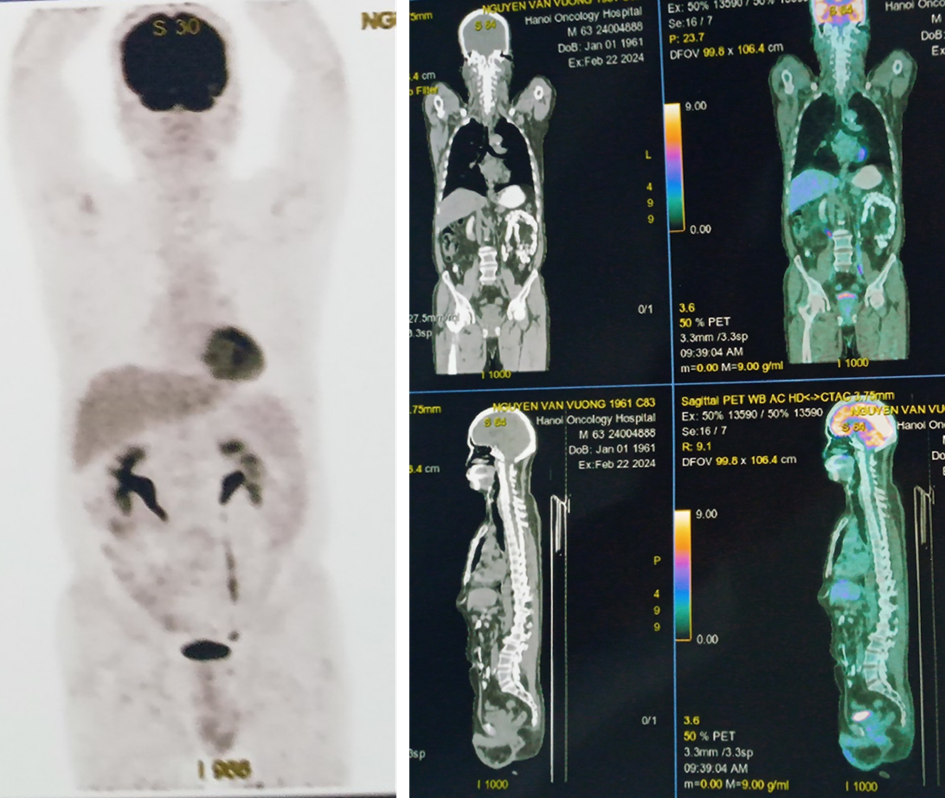

- Hình ảnh chụp PET/CT đánh giá giai đoạn trước điều trị:

Hình 1: Hình ảnh tăng chuyển hoá FDG ở nhiều vị trí hạch cả ở trên và dưới cơ hoành.

- Hình ảnh nhiều hạch cổ (nhóm II, III, IV, V) hai bên ưu thế bên phải, hạch lớn nhất kích thước 24x34 mm, tăng chuyển hoá F-18 FDG (SUVmax: 26.09)

- Hình ảnh nhiều hạch trung thất ở trước các mạch máu lớn, cạnh khí quản, dưới quai, trước và dưới carina, hạch lớn nhất kích thước 25x18mm, tăng chuyển hoá FDG.

- Hình ảnh nhiều hạch rốn phổi, hạch lớn kích thước 15x18mm, tăng chuyển hoá FDG.

- Hình ảnh nhiều hạch hố nách 2 bên, hạch lớn kích thước 21x40mm, tăng chuyển hoá FDG.

- Nhiều hạch ổ bụng quanh động mạch chủ, hạch chậu trong 2 bên, chậu ngoài bên trái, hạch lớn kích thước 39x40mm, tăng chuyển hoá FDG.

- PET/CT: các hạch lớn vùng cổ, nách, trung thất, ổ bụng gần như mất hoàn toàn hoặc giảm kích thước đáng kể, không còn vị trí tăng chuyển hoá FDG bất thường.

Hình 5: Không thấy vị trí tăng chuyển hoá FDG bất thường trên phim PET/CT sau điều trị

- Hình ảnh hạch nách 2 bên, lớn nhất 7mm, hạch chậu phải 11mm, đều không tăng chuyển hoá FDG.

- Chưa phát hiện hình ảnh tổn thương tăng chuyển hoá FDG khú trú, bất thường ở vị trí khác trên PET/CT toàn thân.

 Như vậy bệnh đáp ứng hoàn toàn trên phim PET/CT.